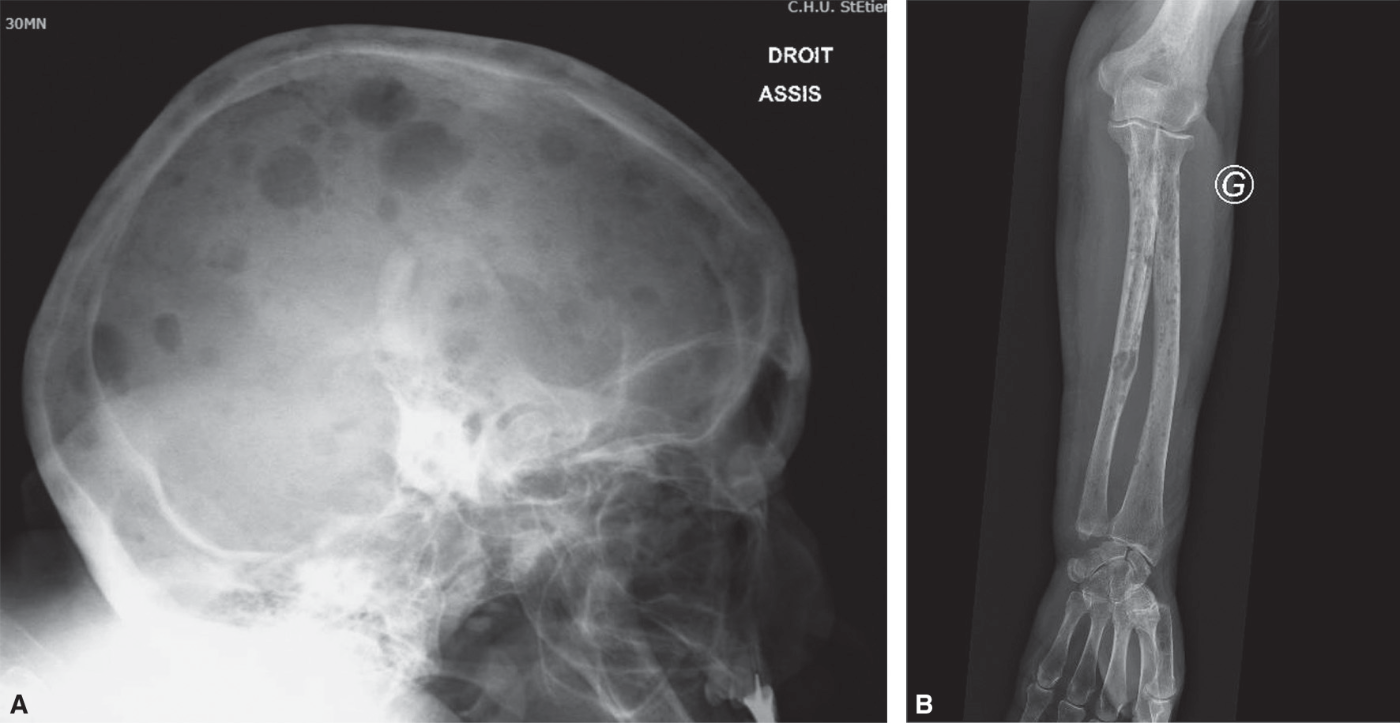

Le myélome est responsable de lésion lytique de type lacune « à l’emporte-pièce », ovalaire ou ronde, sans structure interne visible, bien limitée, sans réaction périphérique ; elle est multiple dans 80 % des cas et tous les os peuvent être atteints (fig. 28.3). Il est parfois difficile de différencier fracture vertébrale d’origine ostéoporotique et fracture liée au myélome. Il est donc nécessaire de toujours réaliser une EPP en cas de fracture ver-tébrale même en cas d’aspect radiologique évocateur de fracture ostéoporotique.

Fig. 28.3 :

Aspect radiographique

A. Lacunes multiples « à l’emporte-pièce » du crâne. B. Lésions lytiques « à l’emporte-pièce » des os de l’avant-bras.